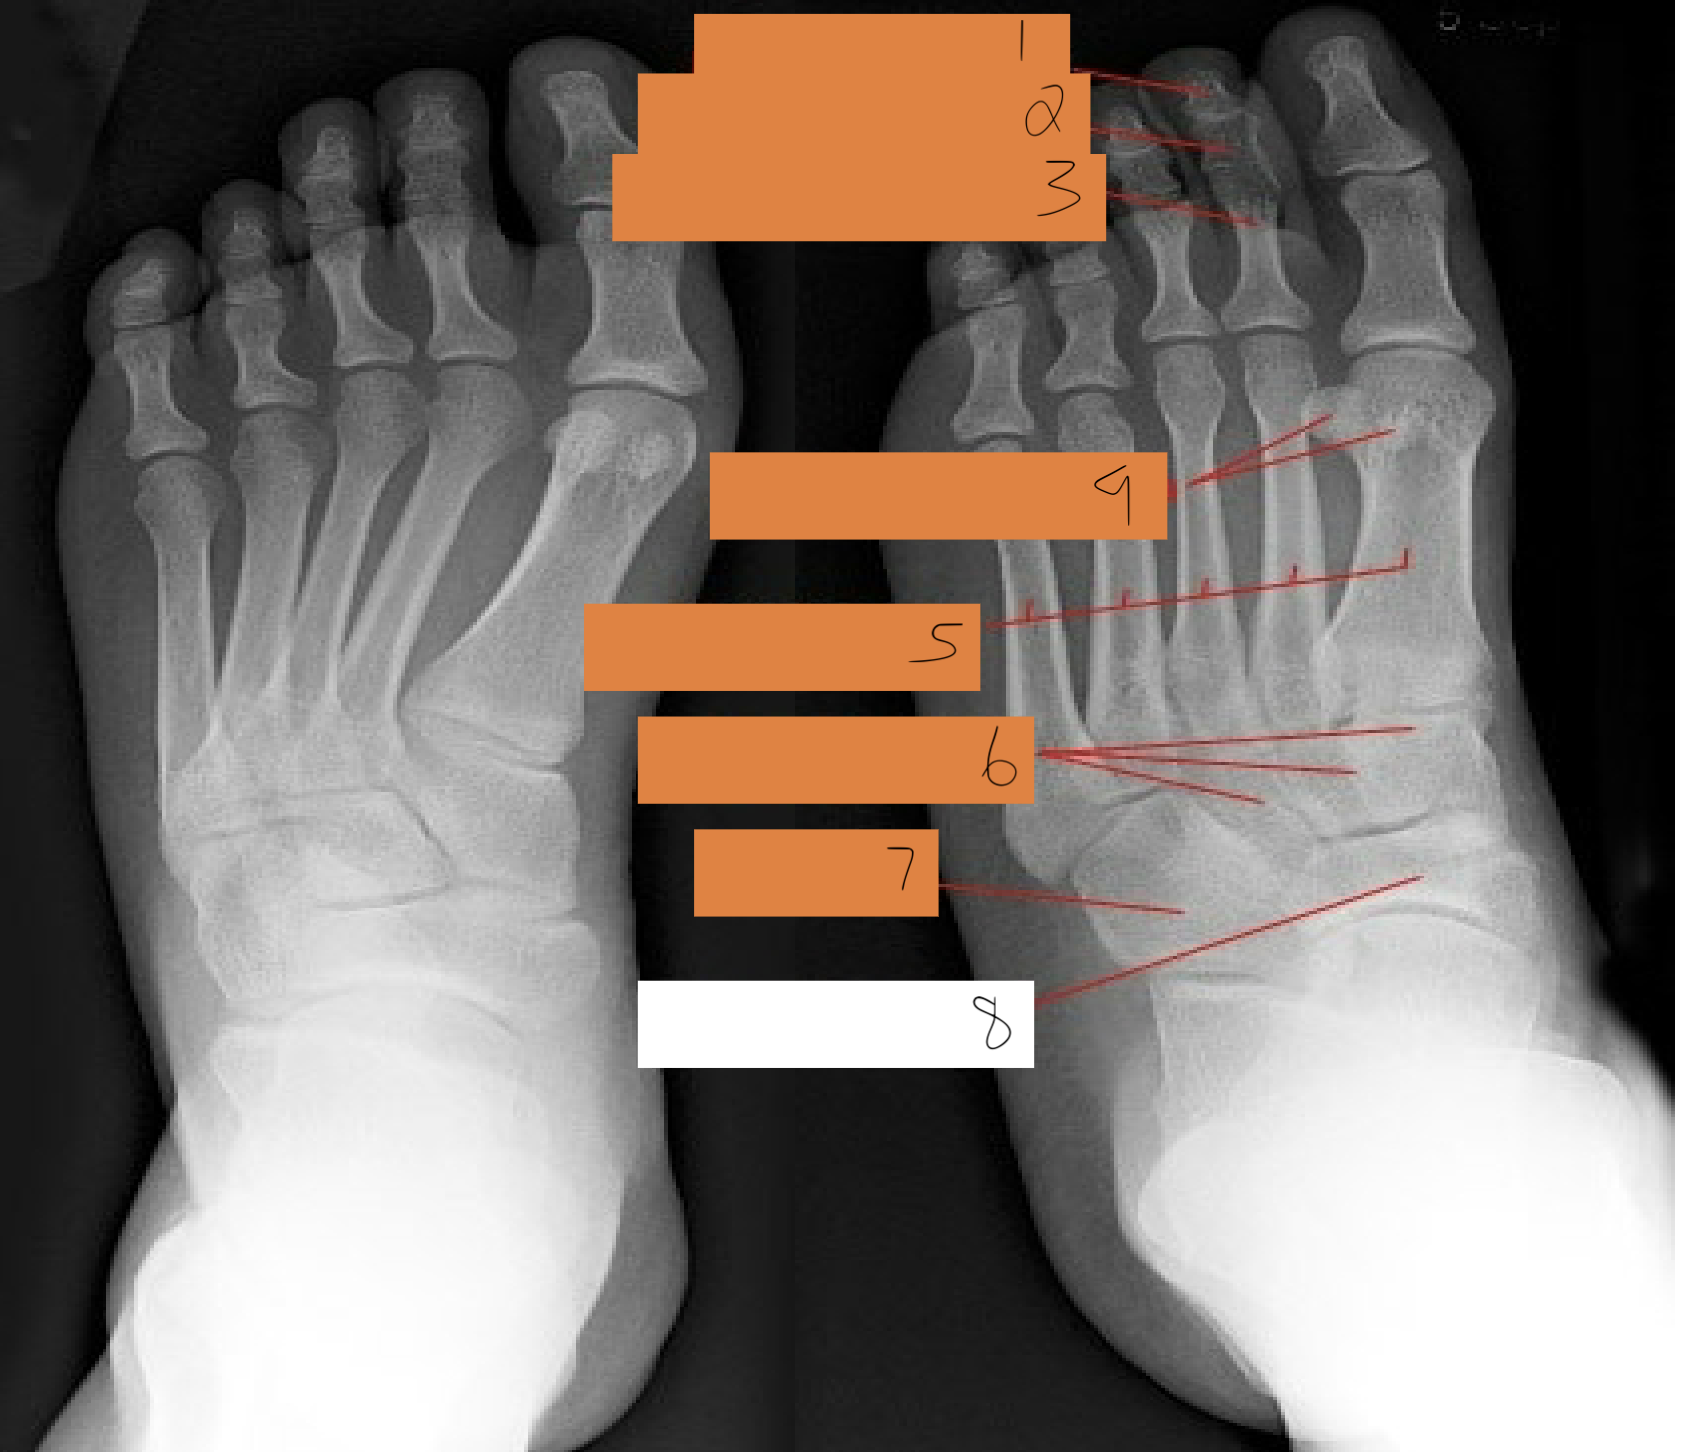

1

interphalangeal joint

2

proximal phalanges 1-5

3

metatarsophalangeal joints

4

sesamoid bones

5

first metatarsals

6

medial cuneiform

7

intermediate cuneiform

8

lateral cuneiform